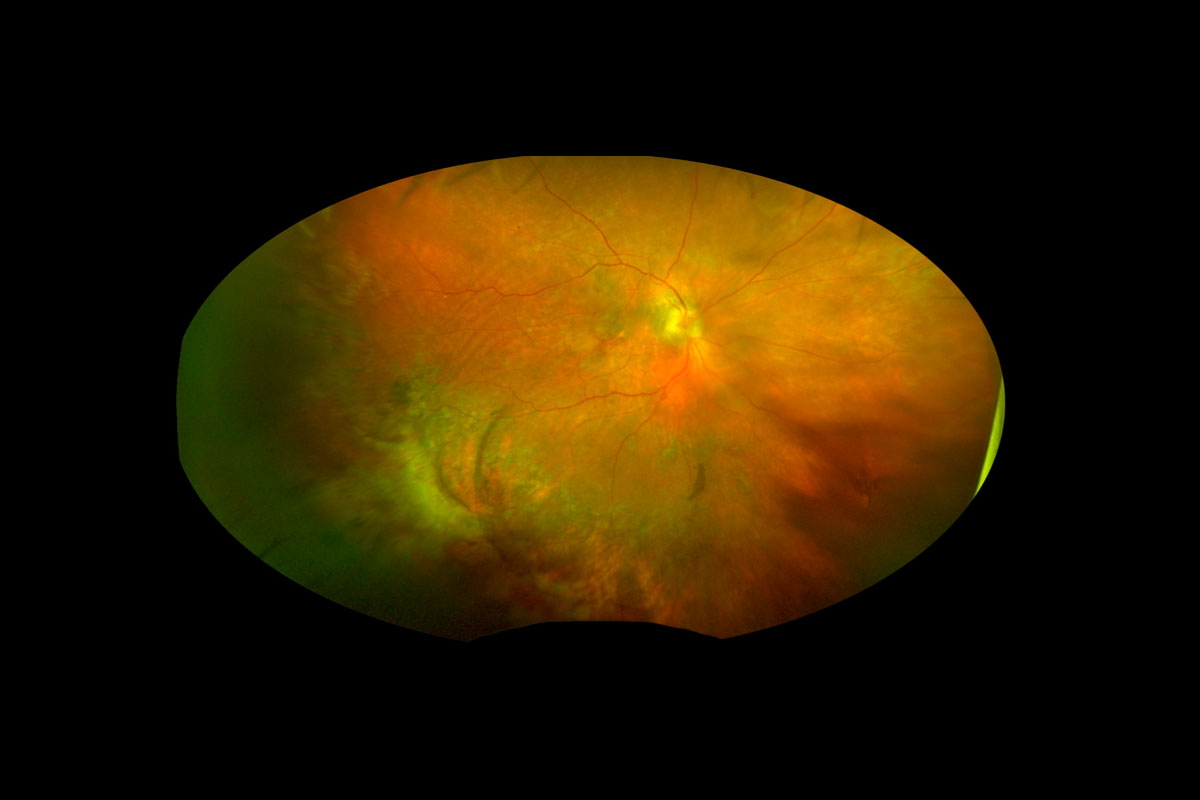

| Figura 3. Estas imágenes son de una paciente de unos 30 años de edad con diabetes tipo 1 mal controlada. Debido a los determinantes sociales de salud (p. ej.: transporte limitado) no tenía atención ocular previa y su ojo derecho quedó ciego debido al glaucoma neovascular. Se presentó cuando el ojo izquierdo, con mejor visión, no logró contar la agudeza visual de los dedos debido a una hemorragia subhialoidea y desprendimiento de retina por tracción con neovascularización extensa y de aspecto maduro del disco y en otros lugares (a la izquierda). Después de una vitrectomía rápida con extracción de la membrana y colocación con láser, recuperó una agudeza visual de 20/25 (a la derecha) que ha mantenido durante años de seguimiento posterior. Foto: Ian C. Han, MD. |